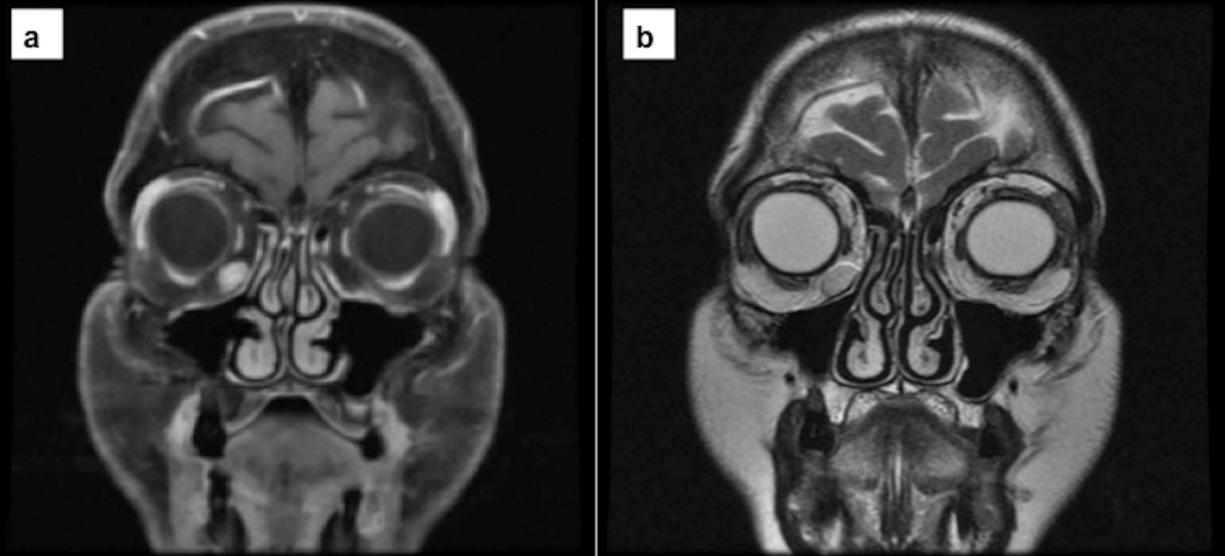

Magnetic resonance imaging (MRI) was performed. It showed a well-localized mass with circumscribed edges and progressive enhancement with gadolinium in sequence T1 (Figure 1a [Fig. 1]) and homogeneous enhancement in sequence T2 (Figure 1b [Fig. 1]).

Figure 1: Magnetic resonance imaging of the coronal section. a) MRI – T1 gadolinium-enhanced showed a well-defined lesion in the inferior orbital rim that was enhanced with contrast. b) MRI – T2 showed a hyperintense lesion. The capsule is shown as well as low-intensity septation.